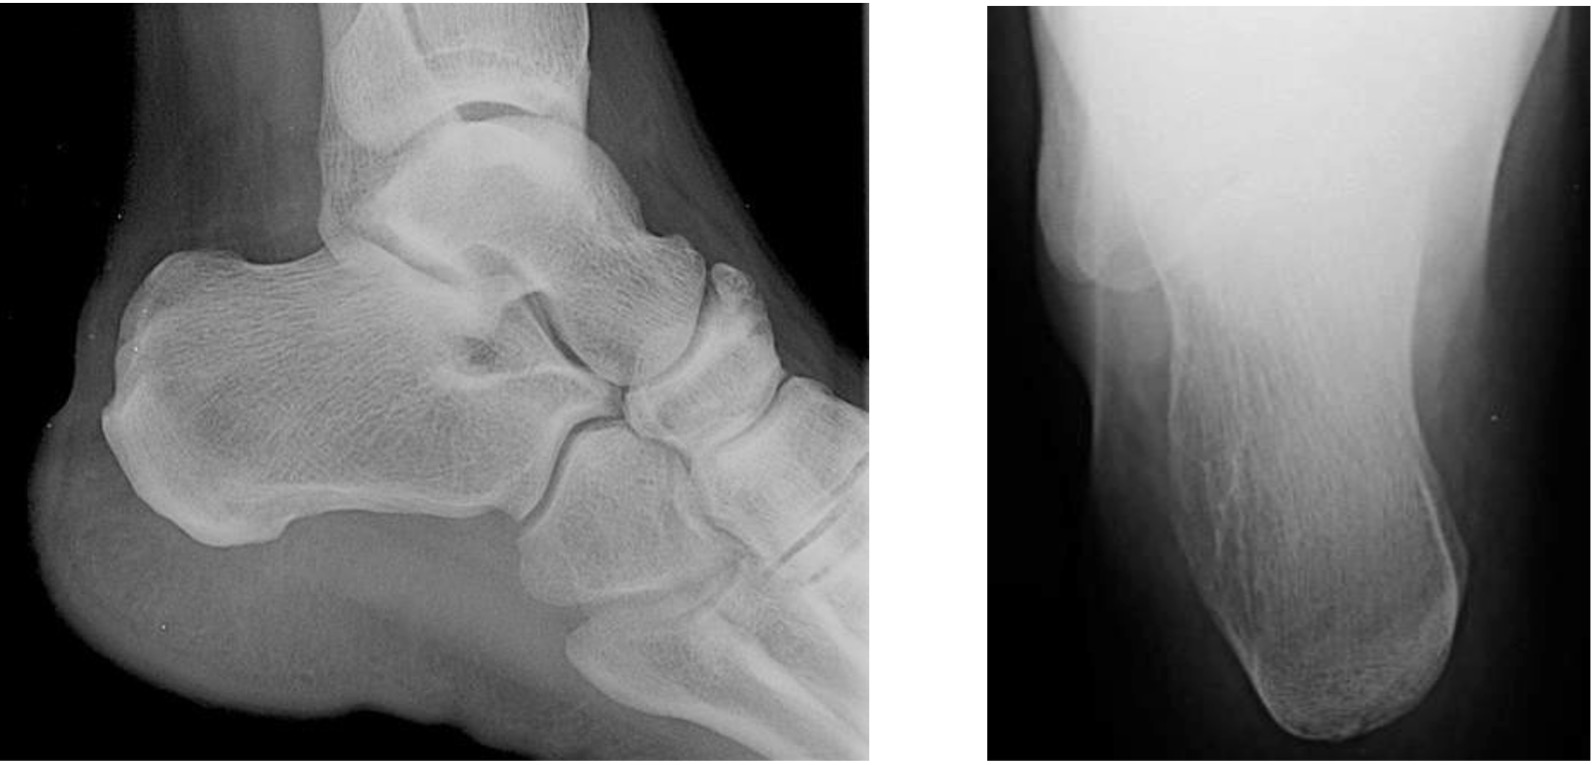

Calcaneal lateral view

Taken with foot in dorsiflexion and X-ray centred 2.5 cm inferior to the medial malleolus.

Calcaneal axial view

Taken with posterior ankle resting on the image receptor, foot dorsiflexed and plantar surface perpendicular to the image receptor. X-ray beam angled 40° cephalad from the long axis of the foot, centred on the base of the 3rd metatarsal.

Calcaneal lateral view Axial view